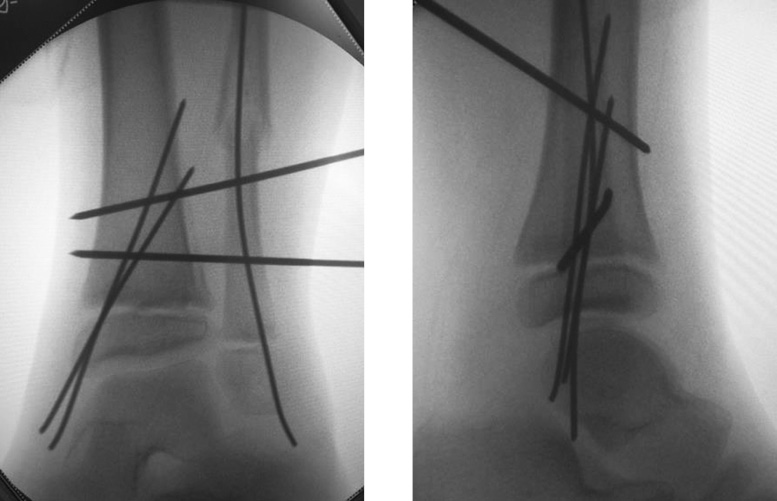

Мальчик, 14 лет, с диагнозом: «Закрытый дистальный остеоэпифизелиз левой большеберцовой кости по Солтеру–Харрису IV типа». Травму получил во время тренировки по самбо. Механизм травмы непрямой, супинационно-эверсионный. В этом возрасте начинает постепенно закрываться эпифизарная пластинка роста, что приводит к изменению ее биомеханических свойств, таких как жесткость, эластичность и упругость. Данная структура становится неравномерной по своей морфологии, и в результате частичного закрытия заднемедиальная зона эпифизарной пластинки становится прочнее, что приводит к возникновению дополнительных плоскостей перелома. Кроме фронтальной и сагиттальной перелом обнаруживается и в поперечной плоскости. В зарубежной литературе такие переломы называются Triplane Fractures [11]. Учитывая тяжесть перелома и внутрисуставной характер, ребенку выполнена компьютерная томография правого голеностопного сустава. Смещение эпифизарной части перелома составило 5,53 мм. Пациенту был выполнен полифокальный остеосинтез спицами. Дополнительная иммобилизация осуществлялась в задней гипсовой лонгете до коленного сустава. Контрольные рентгенограммы выполняли через 4 и 6 нед. после репозиции. Спицы удалены через 6 нед. Конфигурация сустава и функция конечности восстановлены полностью (рис. 5–9).

Рис. 7. Компьютерная томография, эпифиз левой большеберцовой кости / Fig. 7. Computer tomography of the left tibia epiphyseal

Рис. 8. Полифокальный остеосинтез спицами / Fig. 8. Polyfocal osteosynthesis by pins

Рис. 9. Рентгенография голеностопного сустава через 6 недель. Консолидация костных отломков / Fig. 9. X-rays after 6 weeks. Healing of the fracture